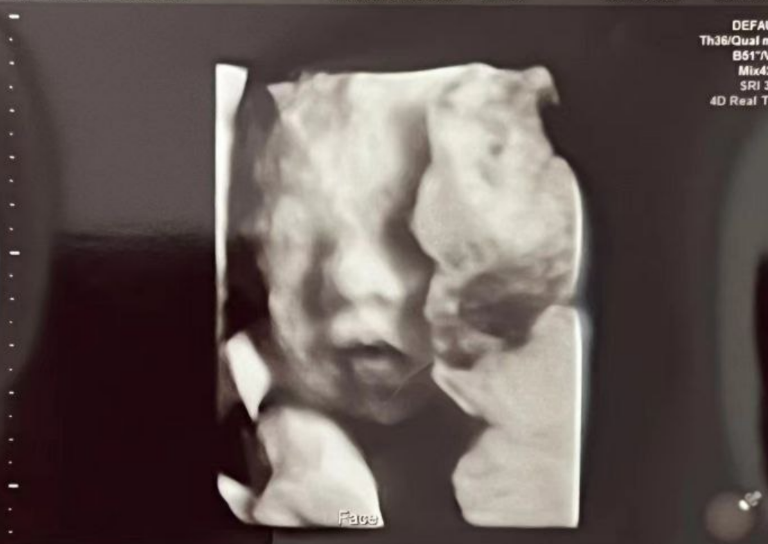

8月26日進行了超聲檢查,當日孕周34週+6天,照到了寶寶清晰的小臉蛋!

2025.9.30|孕28週

寶寶的笑臉越來越清晰,真是幸福又感動~恭喜準媽媽,離相見的日子越來越近啦!